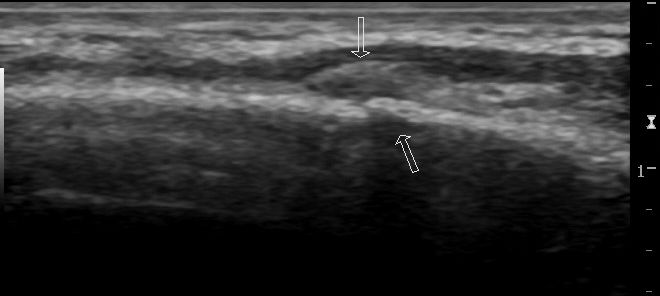

Figure 2:

Magnified image showing subtle cortical lucency of the lower rib suggesting fracture.

Longitudinal view demonstrating a cortical break with overlying crescent shaped hematoma of the same rib fracture as figures 1 and 2.

Using a linear probe, place it perpendicular to the rib obtaining a transverse view and tracing the length of the rib at the site of highest tenderness. Observe for cortical disruption and surrounding hematoma as this can suggest a rib fracture. A longitudinal view should also be obtained for confirmation of findings.